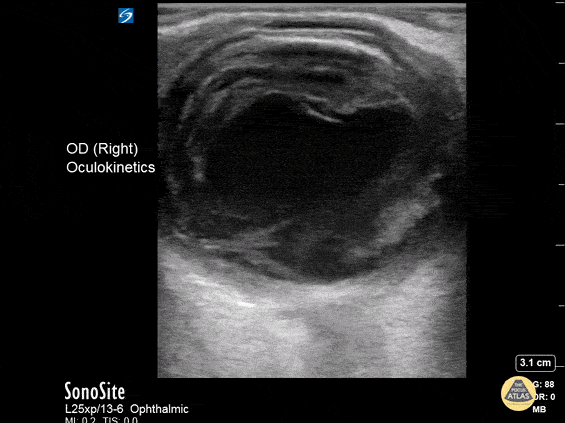

A 43 year old male with 3 days of painful right eye vision loss, fever, and URI symptoms presented to the emergency department. POCUS demonstrates echogenic swirl within the vitreous cavity. The patient was diagnosed with endogenous endophthalmitis caused by Klebsiella Pneumoniae. Contributor: Hyun J. Yi (John), D.Sc, PA-C, MAJ, USA, Emergency Ultrasound Fellow, Madigan Army Medical Center, Joint Base Lewis-McChord, WA